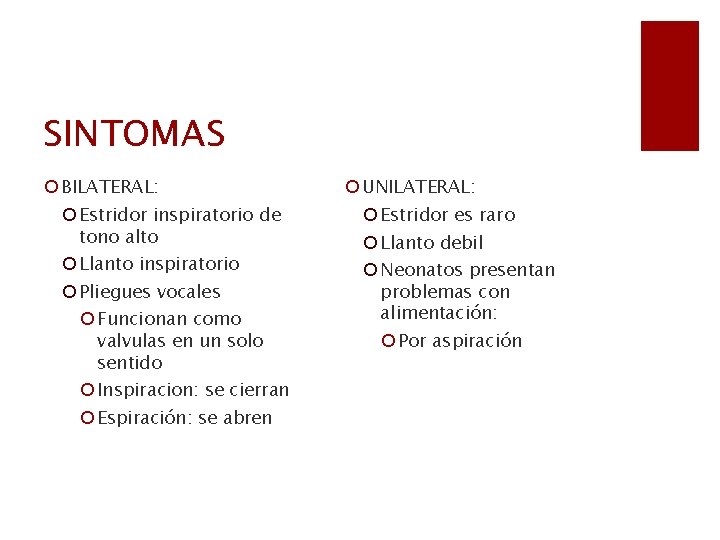

SINTOMAS ¡ BILATERAL: ¡ Estridor inspiratorio de tono alto ¡ Llanto inspiratorio ¡ Pliegues vocales ¡ Funcionan como valvulas en un solo sentido ¡ Inspiracion: se cierran ¡ Espiración: se abren ¡ UNILATERAL: ¡ Estridor es raro ¡ Llanto debil ¡ Neonatos presentan problemas con alimentación: ¡ Por aspiración